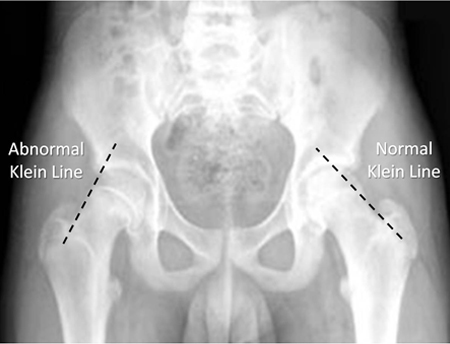

2. Diagnosing SCFE on plain radiographs is accomplished by drawing a parallel line from the lateral femoral neck towards the femoral head. This line is called Klein’s Line. In normal patients, this line should intersect the lateral portion of the femoral head. In SCFE patient, it does not.